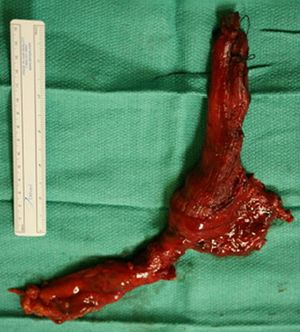

말기 식도이완불능증은 심하게 확장되고 뒤틀린 식도를 특징으로 한다.[12] 이전에 치료를 받았음에도 불구하고 증상이 재발하고 영양 상태가 악화된 환자에게는 식도절제술이 필요할 수 있다.[13][14][15]